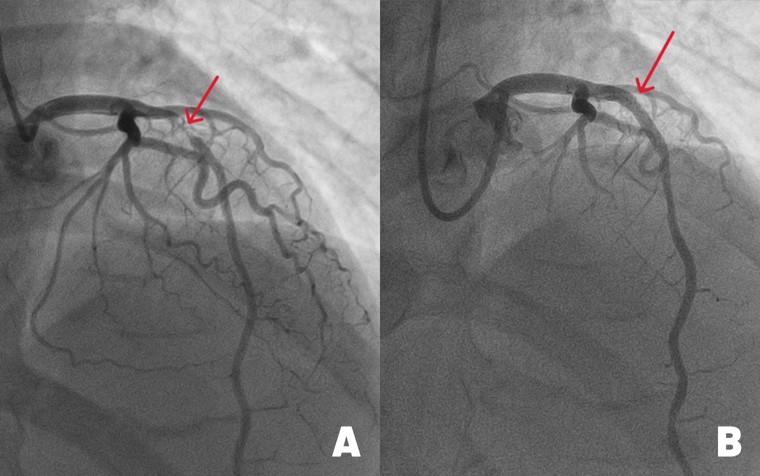

Hình ảnh động mạch liên thất trước (mạch máu chính nuôi tim) bị đứt do tắc nghẽn nặng (hình A) và sau khi được tái thông nhờ đặt stent kích thước lớn. Ảnh: BVĐK Tâm Anh. |

Kết quả chụp mạch vành cho thấy, động mạch liên thất trước hẹp đến 99%. May mắn là vẫn có một dòng chảy nhỏ giúp cầm cự, tưới máu tạm thời nuôi cơ tim. “Với tình trạng này, cần can thiệp đặt stent càng sớm càng tốt cho bệnh nhân để tái thông dòng máu, tránh nguy cơ đột quỵ tim có thể xảy đến bất cứ lúc nào”, bác sĩ Long cho biết.

Với kinh nghiệm xử lý những ca hẹp nặng mạch vành, bác sĩ Long và êkip luồn ống thông từ động mạch quay (ở cổ tay) tới chỗ xuất phát động mạch vành trái. Sau đó, luồn sợi dẫn 0.35mm qua vị trí hẹp ở động mạch liên thất trước. Dưới sự hỗ trợ của hệ thống siêu âm trong lòng mạch (IVUS), êkip đo đạc chính xác đường kính mạch máu, đặt một stent phủ thuốc, nong nở rộng lên đến 4.0 mm, áp sát thành mạch, ngăn nội mạc mạch máu tăng sinh quá mức. Điều này giúp giảm nguy cơ tái hẹp trong stent, tái phát nhồi máu cơ tim xuống thấp (dưới 2%).